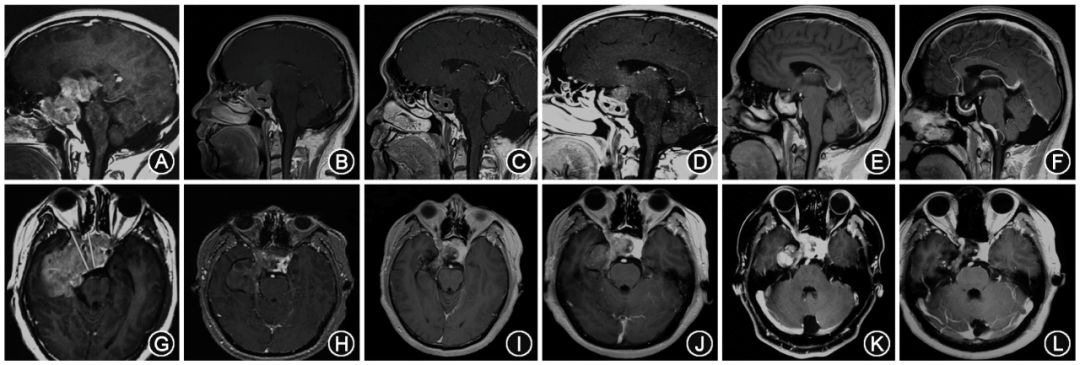

患者平时容易发困,无头痛、面容改变、烦渴多尿,不伴有向心性肥胖、男性乳房发育、肢端肥大等症状。体格检查:神志清,右眼前指数,几近失明,左眼视力0.4,左颞偏盲,双侧瞳孔对称,光反射存在,四肢活动自如。内分泌化验结果:血清催乳素(PRL)水平>470μg/L(正常范围4.04~15.02 μg/L),游离T3水平略低,其余激素水平正常范围。头颅磁共振成像(MRI)显示:鞍区巨大占位,大小约为7.6cm× 5.8cm× 3.8cm,向上突入三脑室,向下侵袭蝶窦和斜坡,向右侧侵犯海绵窦并包绕颈内动脉,肿瘤还突入颅内,于右颞形成巨大占位(图1)。

图1. 药物治疗后催乳素腺瘤患者肿瘤体积在增强MRI时的变化(矢状位和轴位)。

A~C,G~I:溴隐亭治疗;D~F,J~L:卡麦角林治疗。

MRI矢状位(图1A~F)和轴位(图1G~L)来说明肿瘤体积的动态变化。根据体积测量结果,颅内部分最初体积为45.8cm³服药1个月后颅内部分体积缩小至20.7cm³,缩小率为55%(图1H)。之后,肿瘤体积持续缩小,至2013年8月31日为5.8cm³(图2A)。另一个改善明显的是鞍内肿瘤的高度,治疗前为6cm,服药1个月时为3.5cm,快速有效解除了视神经的压迫,之后肿瘤高度持续缩小至1.3cm(图1A~C,图2B)。其鞍内部分的肿瘤体积也明显缩小,治疗前为19.3cm³,2013年8月31日为2cm³(图2A)。然而,海绵窦部分的肿瘤体积变化不是很明显,治疗前为3.7cm³,2013年8月31日为3.5cm³,说明海绵窦部分肿瘤对溴隐亭治疗具有某种程度的耐药性(图2A)。

服药到第8个月,即2013年9月在足量溴隐亭继续服用的情况下,发现肿瘤反而增大,出现迟发耐药的现象。其颅内肿部分的肿瘤体积从5.8cm³增加至14.4cm³,同时鞍内部分的肿瘤体积亦有所增大,从2cm³增加至5.6cm³(图1D,J)。从2013年10月开始,患者开始接受卡麦角林治疗 (卡麦角林的初始治疗剂量为每次0.5mg,2次/周,无药物不良反应。2周后剂量增加至每次1mg,2次/周),肿瘤体积又开始缩小,直至肿瘤几近完全消失(图2C),PRL一直维持在正常的低限水平。随访至2014年6月,其中鞍内部分和颅内部分肿瘤几近消失,海绵窦部分肿瘤残留(图1F,L)。